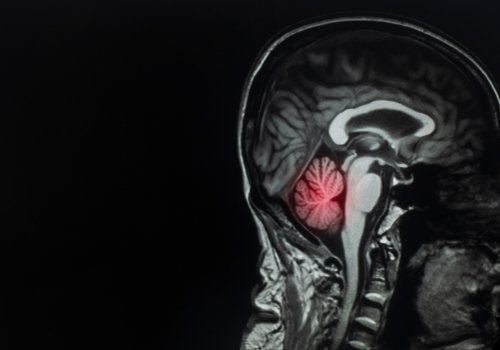

Métastases cérébrales : qu'est-ce que c'est et comment les traiter ?

Les métastases cérébrales constituent la forme de tumeur cérébrale la plus fréquente. Elles représentent un véritable défi pour les médecins. Elles représentent environ 90 % de tous les cas de tumeurs cérébrales.

En ce sens, il est intéressant de noter que la répartition des métastases cérébrales est proportionnelle au débit sanguin dans la région en question, avec les pourcentages suivants :

- 80% des lésions dans le cerveau

- 15% dans le cervelet

- 5 % dans le tronc cérébral